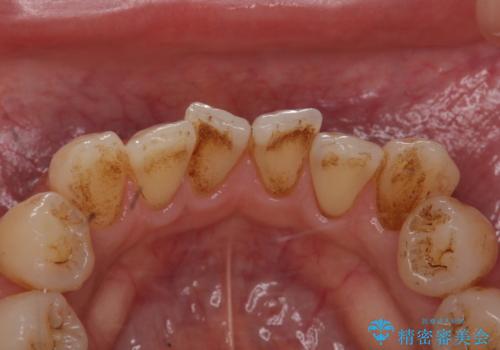

専門的なクリーニング(PMTC)で着色を除去!!

- 普段からよくお茶を飲む為、茶渋がついて歯の着色が気になり来院されました。

PMTC(歯科医院で行うプロフェッショナルクリーニング)をおすすめしました。

歯の着色と汚れもとれ、ツルツルになったと喜んでいただけました。